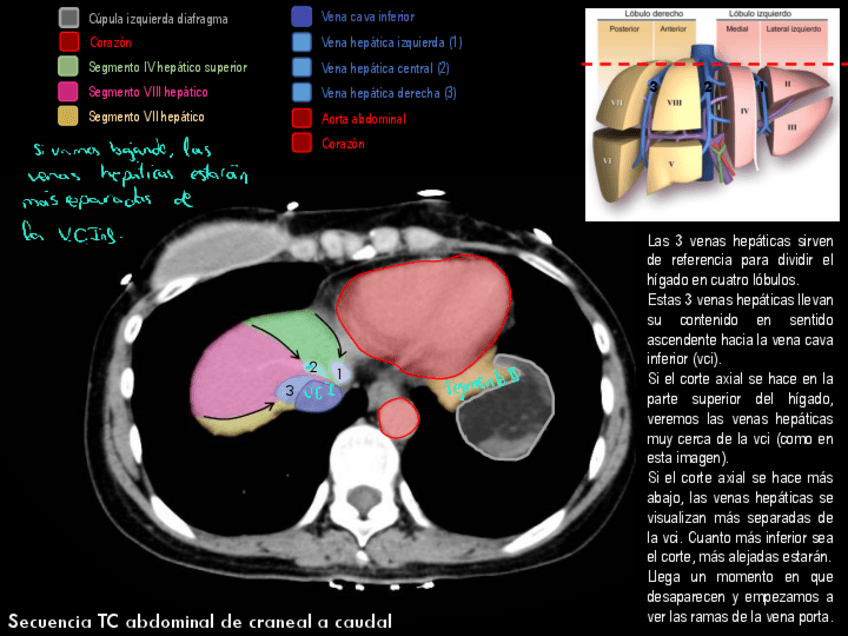

He publicado nuevos apuntes de Anatomía por la imagen: TCSegmentacion-hepatica-y-digestivo.pdf

28 páginas

He publicado nuevos apuntes de Anatomía por la imagen: Imagenes-TC-RM-abdominal.pdf

63 páginas